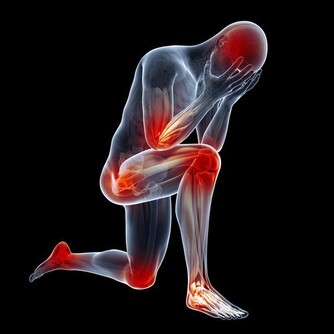

然而一次的舌頭割傷後,傷口卻一直都沒好轉甚至愈來愈嚴重,

還長了顆水泡,且經常散發出膿液,後來確診王先生罹患了「舌癌」。

原來,當王先生的舌頭被割破時,他並沒有因而忌口,

反而繼續吃香喝辣反覆刺激傷口,進而導致舌頭形成癌變。